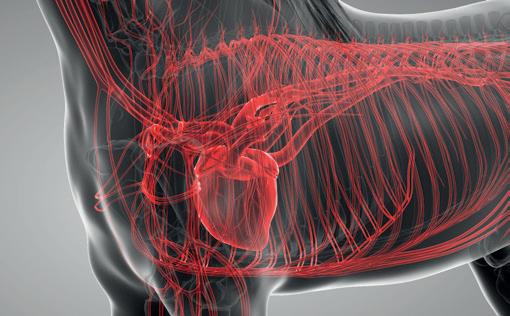

Horses’ limbs consist of dozens of muscles, bones, tendons, ligaments, and joints that allow the horse to move as well as support its body weight. The limbs function to provide thrust and movement while absorbing impact and bearing weight. Most of the horse’s weight is supported by the fore limbs, while the propulsion of the horse is provided by the hind limbs. In addition, the horse has two apparatuses referred to as the stay apparatus and suspensory apparatus. The stay apparatus allows major joints in the limbs to lock so that the horse may rest and relax while standing. The suspensory apparatus is designed to absorb shock, carry the horse’s weight, and prevent the overextension of joints. Finally, the hooves are important structures that maintain support and traction as well as provide additional shock absorption.

Since the cardiovascular system provides blood supply throughout the body, by responding to various stimuli, it can control the velocity and amount of blood carried through the vessels, thus, delivering oxygen, nutrients, hormones, and other important substances to cells and organs in the body. It plays a very important role in meeting the body’s demands during exercise, stress, and activity.

Exercise is used to increase the body’s ability to withstand repeated bouts of similar exercise with less impact. With a strong and healthy cardiovascular system, there is an improved ability of the musculoskeletal system receiving oxygen, thus, allowing muscles to better their capacity to use oxygen and energy. However, the adaptation period for each of these physiological systems do differ as the cardiovascular system adapts faster compared to the musculoskeletal system. This is often an overlooked consideration when developing training programmes for horses.